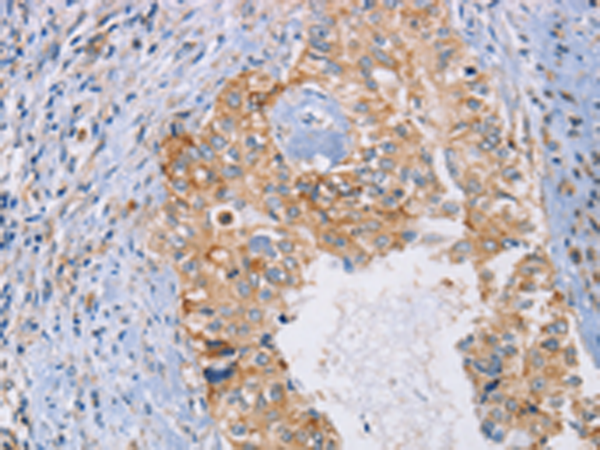

分类: 科研抗体货号: P11231别名: ACPT; AI1J应用: IHC反应种属: Human, Mouse